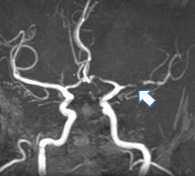

下の画像の患者さんは、突然右手足に力が入らなくなったが少し経って治ったという症状で受診しました。脳内の動脈を描出するMRA検査で左中大脳動脈に狭窄部位(矢印)が見られます。狭くなった動脈の末梢に頭皮の動脈でバイパスを作る手術(浅側頭動脈―中大脳動脈吻合術)を行い、脳梗塞を発症する事なく元気に過ごされています。